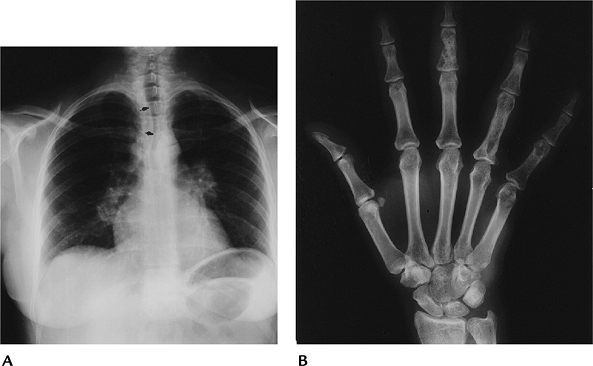

![]() |

FIGURE 15-42 Sarcoidosis. (A) PA radiograph of the chest showing bilateral hilar and right paratracheal adenopathy. Note the tracheal deviation (arrows). (B)

Radiograph of the right hand showing lacelike trabecular pattern and cystic changes in the third middle phalanx and fourth proximal phalanx. |